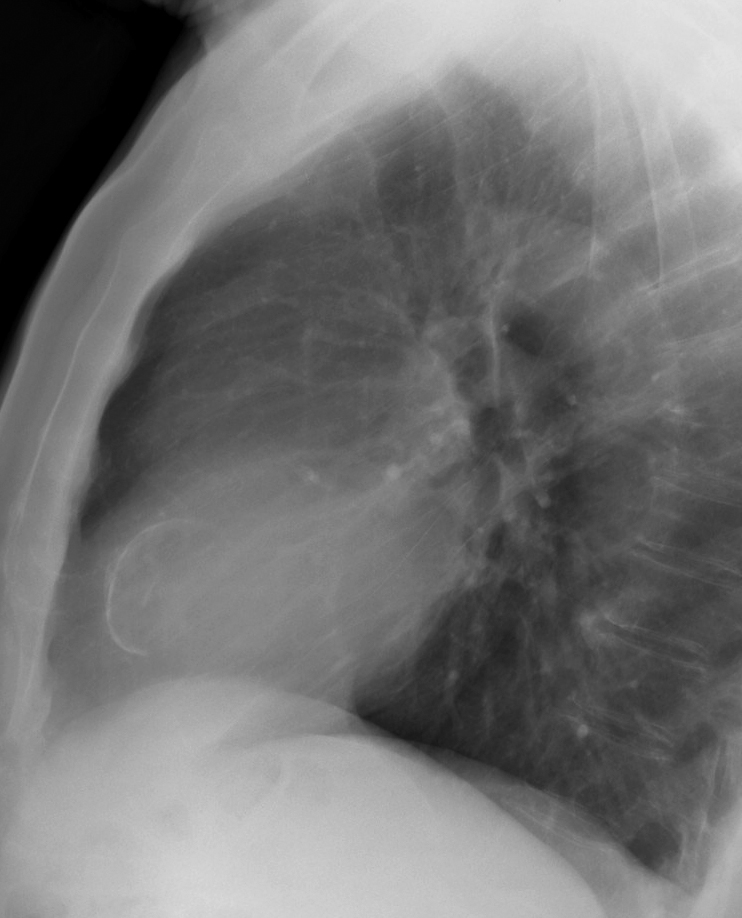

Gallery Cardiac Other LV calcific lat

LV calcific lat